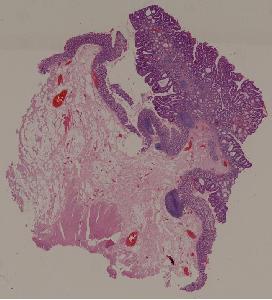

28. Adenoma of the colon

29. Adenocarcinoma of the colon